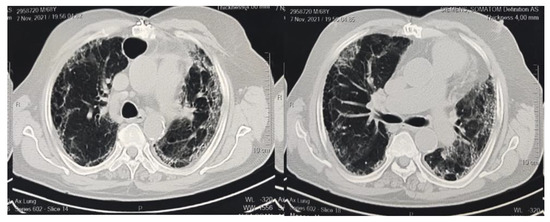

| Broncho vascular bundle distortion, n% | 25 (53.1%) | 19 (35.8%) | 0.749 |

| Traction bronchiectasis, n% | 37 (78.7%) | 31 (58.4%) | 0.451 |

| Fibrotic strips, n% | 7 (14.8%) | 4 (7.5%) | 0.529 |

| Architectural distortion, n% | 29 (61.7%) | 22 (41.5%) | 0.532 |

| Interlobar septal thickening, n% | 10 (21.2%) | 12 (22.6%) | 0.422 |

| Honeycombing appearance, n% | 8 (17.02%) | 15 (28.3%) | 0.167 |